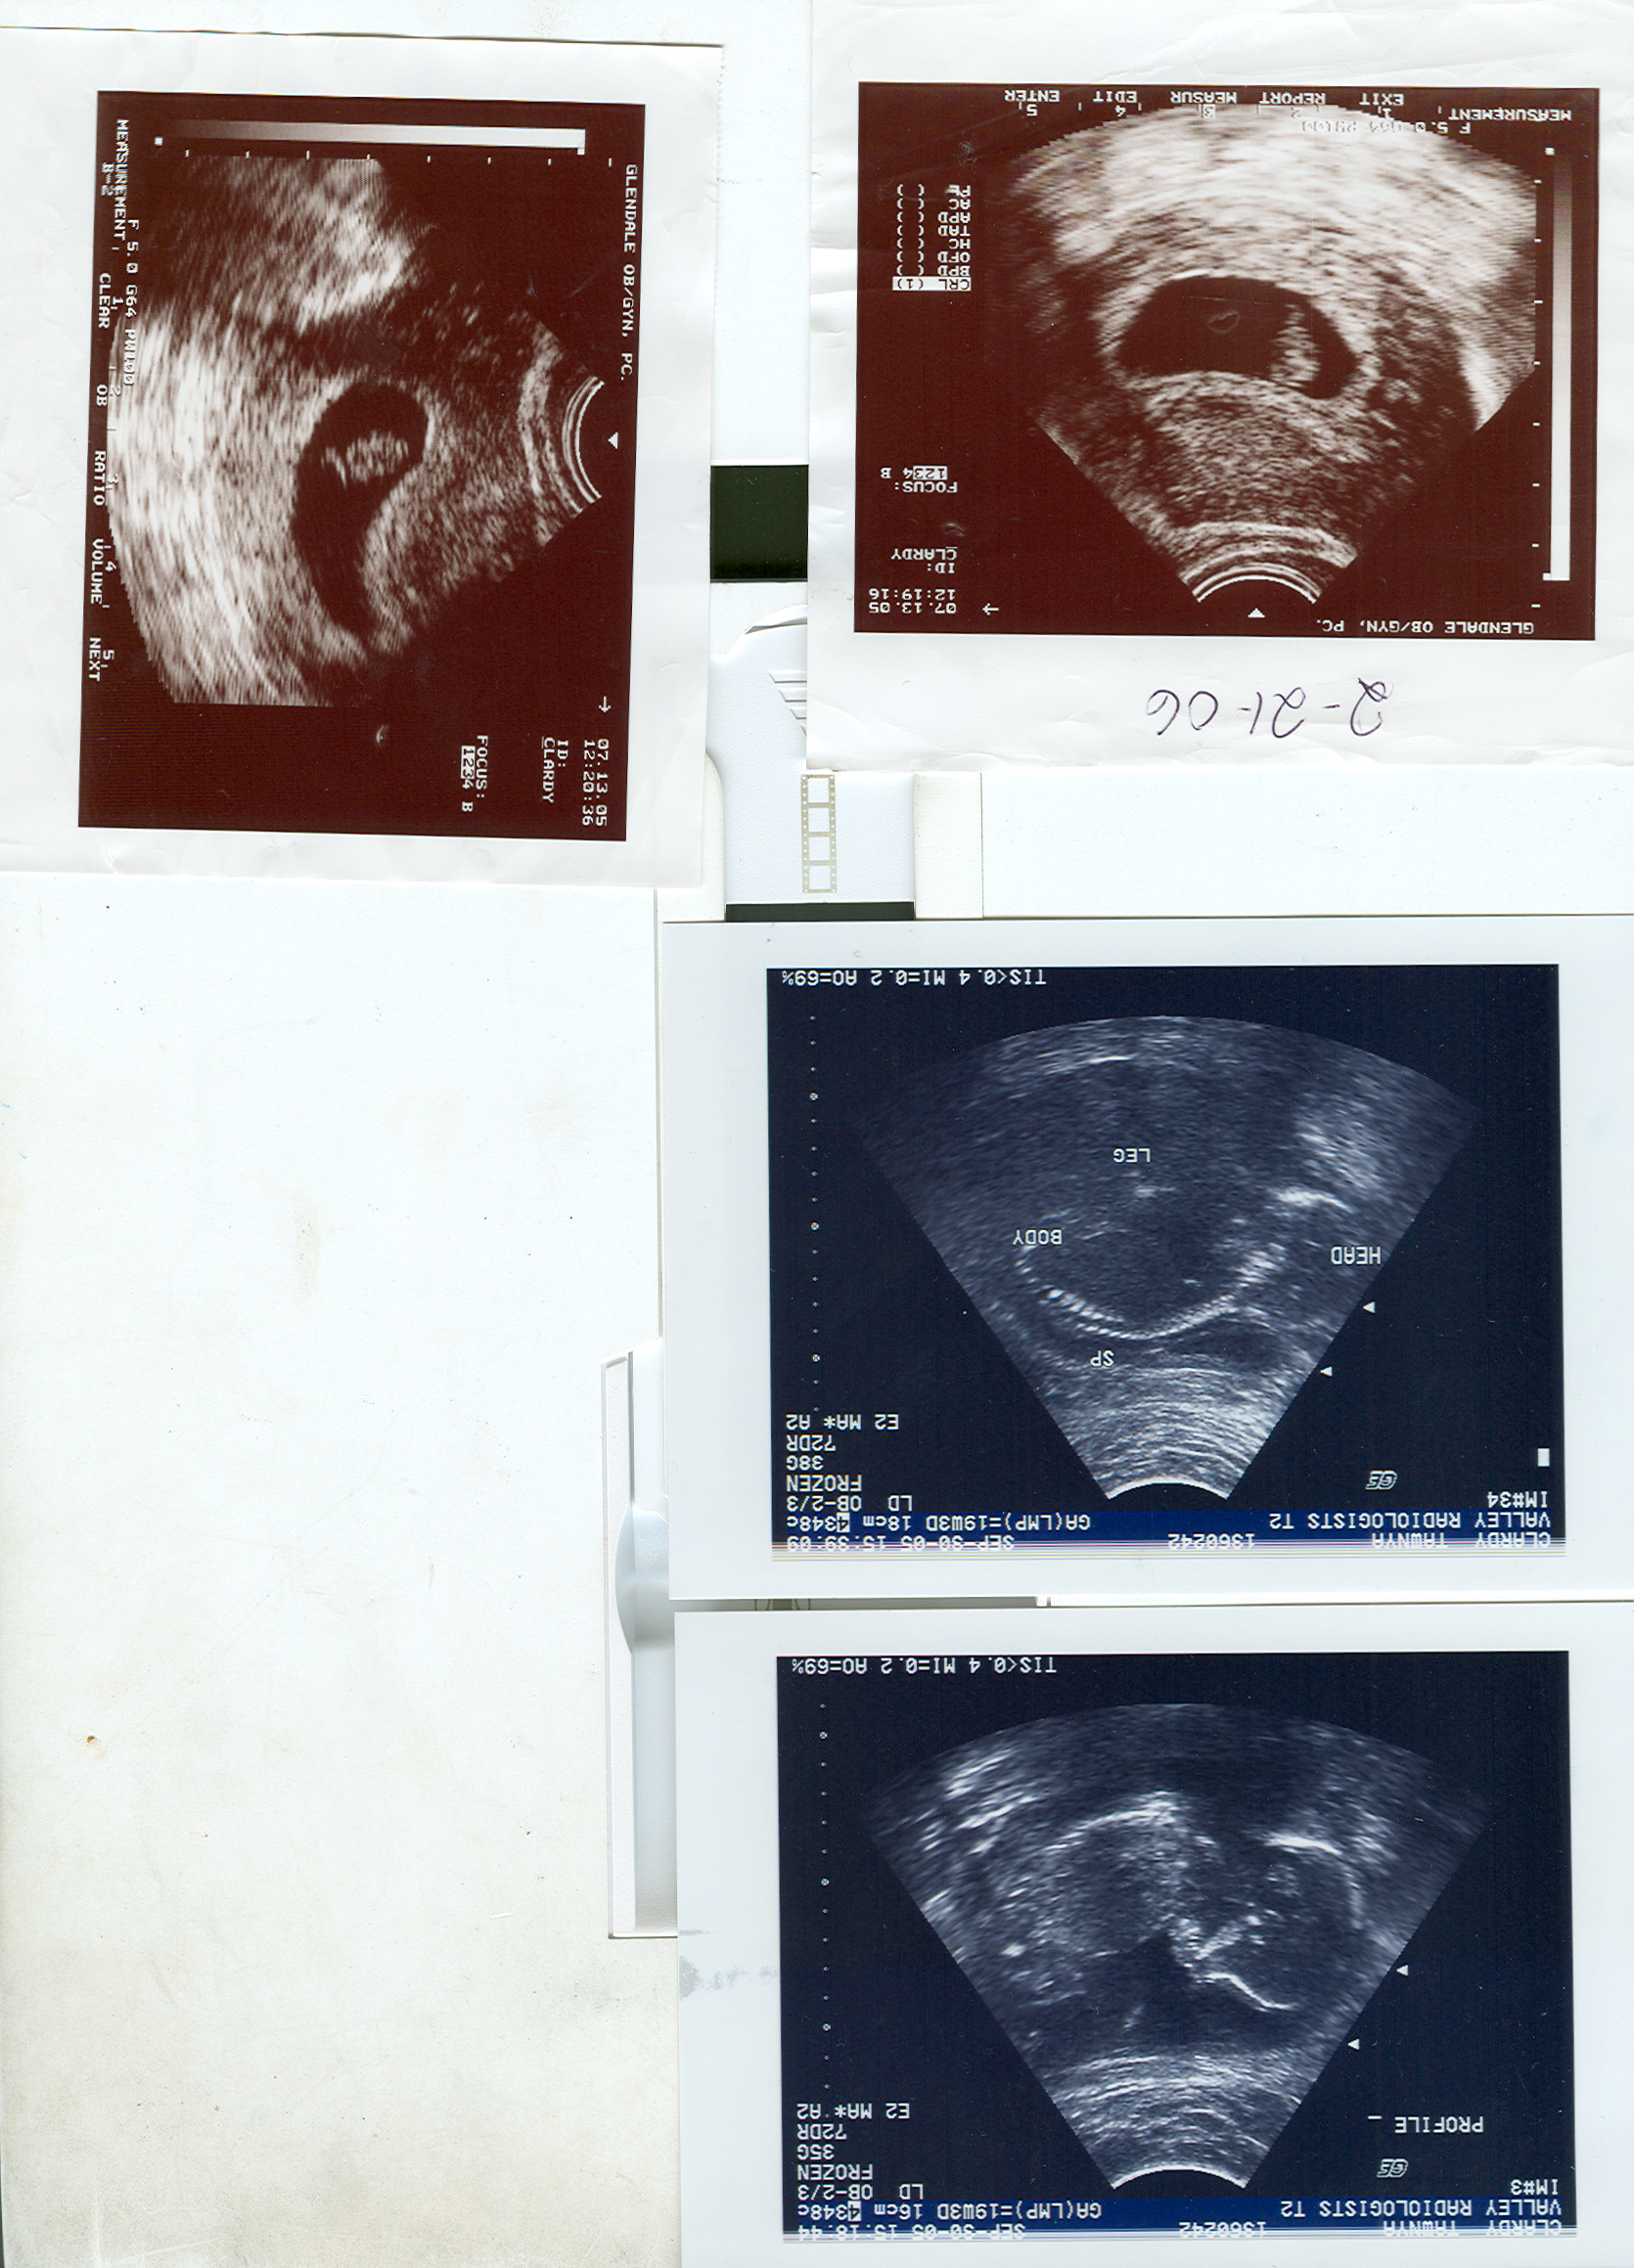

Welcome, brothers and sisters of the household! Behold, the first images of our heir, Alexander Michael, future warrior of Inverted. My apologies for the file size; when I have the time, I will edit them into four separate files. The top pictures are from 7 weeks, and the booton are from 18 weeks. Southern Crusades weekend, I will be 24-25 weeks. He's due Estrella weekend, around the 15th-27th of February. Huzzah!